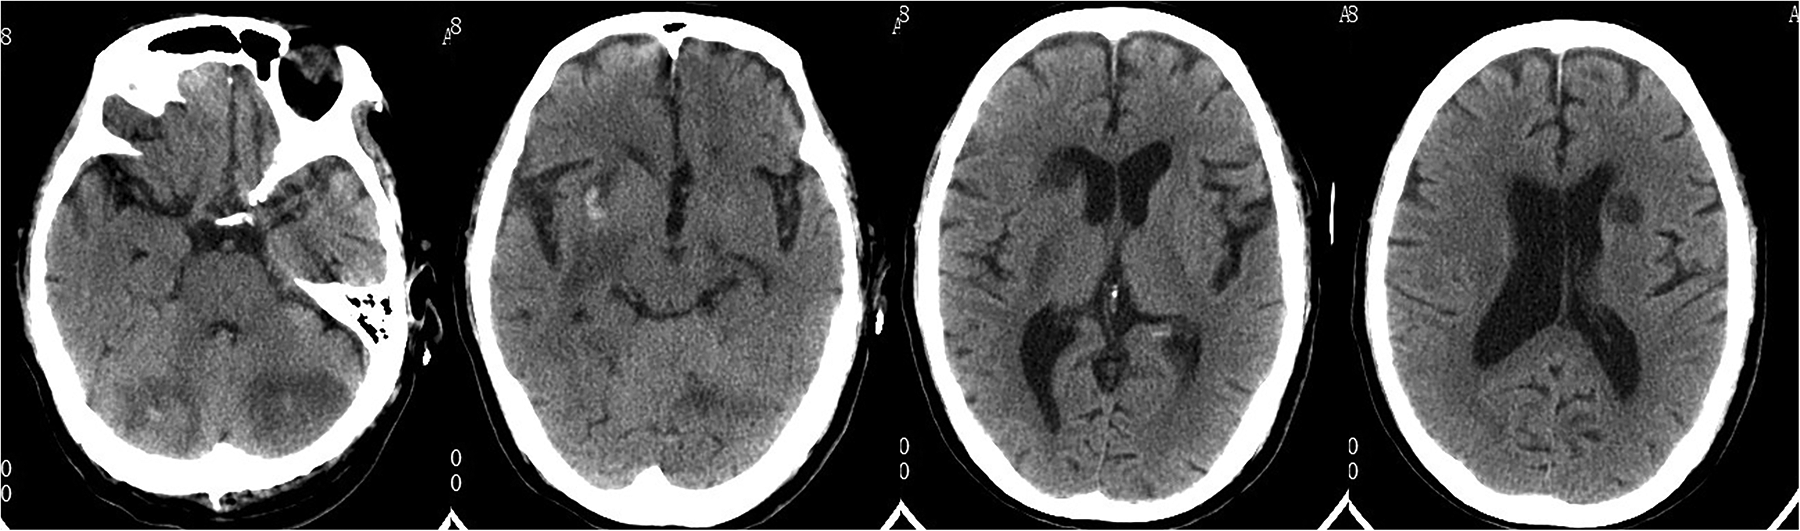

Head CT showed new hemorrhage in the right basal ganglia (Figure 3). Lumbar puncture and mNGS of Cerebrospinal Fluid (CSF), peripheral blood, and bronchoalveolar lavage fluid were performed. The mNGS results were as follows: 434 sequences of Aspergillus fumigatus in cerebrospinal fluid, 12 sequences of Aspergillus fumigatus in peripheral blood, and no Aspergillus fumigatus detected in bronchoalveolar lavage fluid (Table 1). Subsequent to the mNGS finding, a follow-up echocardiogram was done which revealed a mass on the mitral valve of size 1.38 cm × 2.10 cm suggestive of a vegetation (Figure 1C). Next, voriconazole was initiated to treat suspected Aspergillus endocarditis with embolization and meningoencephalitis. The patient remained comatose, and on the 14th day, with bilateral pupillary dilation and a Glasgow Coma Scale score of 3, the family opted for palliative care. CSF and blood bacterial cultures were negative, and the serum G + GM test was also negative. The G test, also known as the 1,3-β-D-glucan test, detects the 1,3-β-D-glucan component in fungal cell walls. After phagocytes engulf fungi, they continuously release this substance, increasing its concentration in blood and bodily fluids. 1,3-β-D-glucan specifically activates the G factor in Limulus amoebocyte lysate, leading to the coagulation of the lysate. The GM test detects galactomannan (GM), a polysaccharide widely found in the cell walls of Aspergillus and Penicillium species. Galactomannan is released from the tips of fragile hyphae during hyphal growth and is one of the first antigens to be released. The G + GM test is mainly used clinically for the early diagnosis of invasive fungal infections, particularly invasive aspergillosis (6).

Figure 3

Follow-up head CT revealed multiple cerebral infarctions in the bilateral periventricular regions, basal ganglia, and cerebellum, with a small amount of bleeding in the right basal ganglia infarction area.